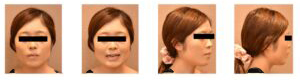

治療前-治療後

(治療前:写真左)

咬筋が肥大し、エラが張っています。前歯が噛み合わさっていません。おちょぼ口で、口元に歪みがあります。

(治療後:写真右)

矯正治療終了後は歯列全体で噛みあっているため咬筋の肥大がなくなり、すっきりしたお顔立ちになりました。リップラインがきれいに広がり、口元の歪みが改善しました。横顔もメリハリができ、バランスが整いました。